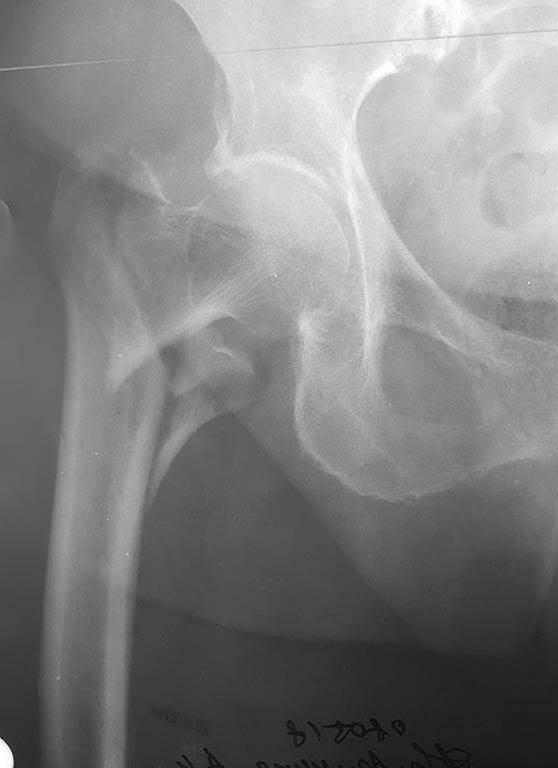

Re: БИОС PFNA варусного бедра

Первичный снимок